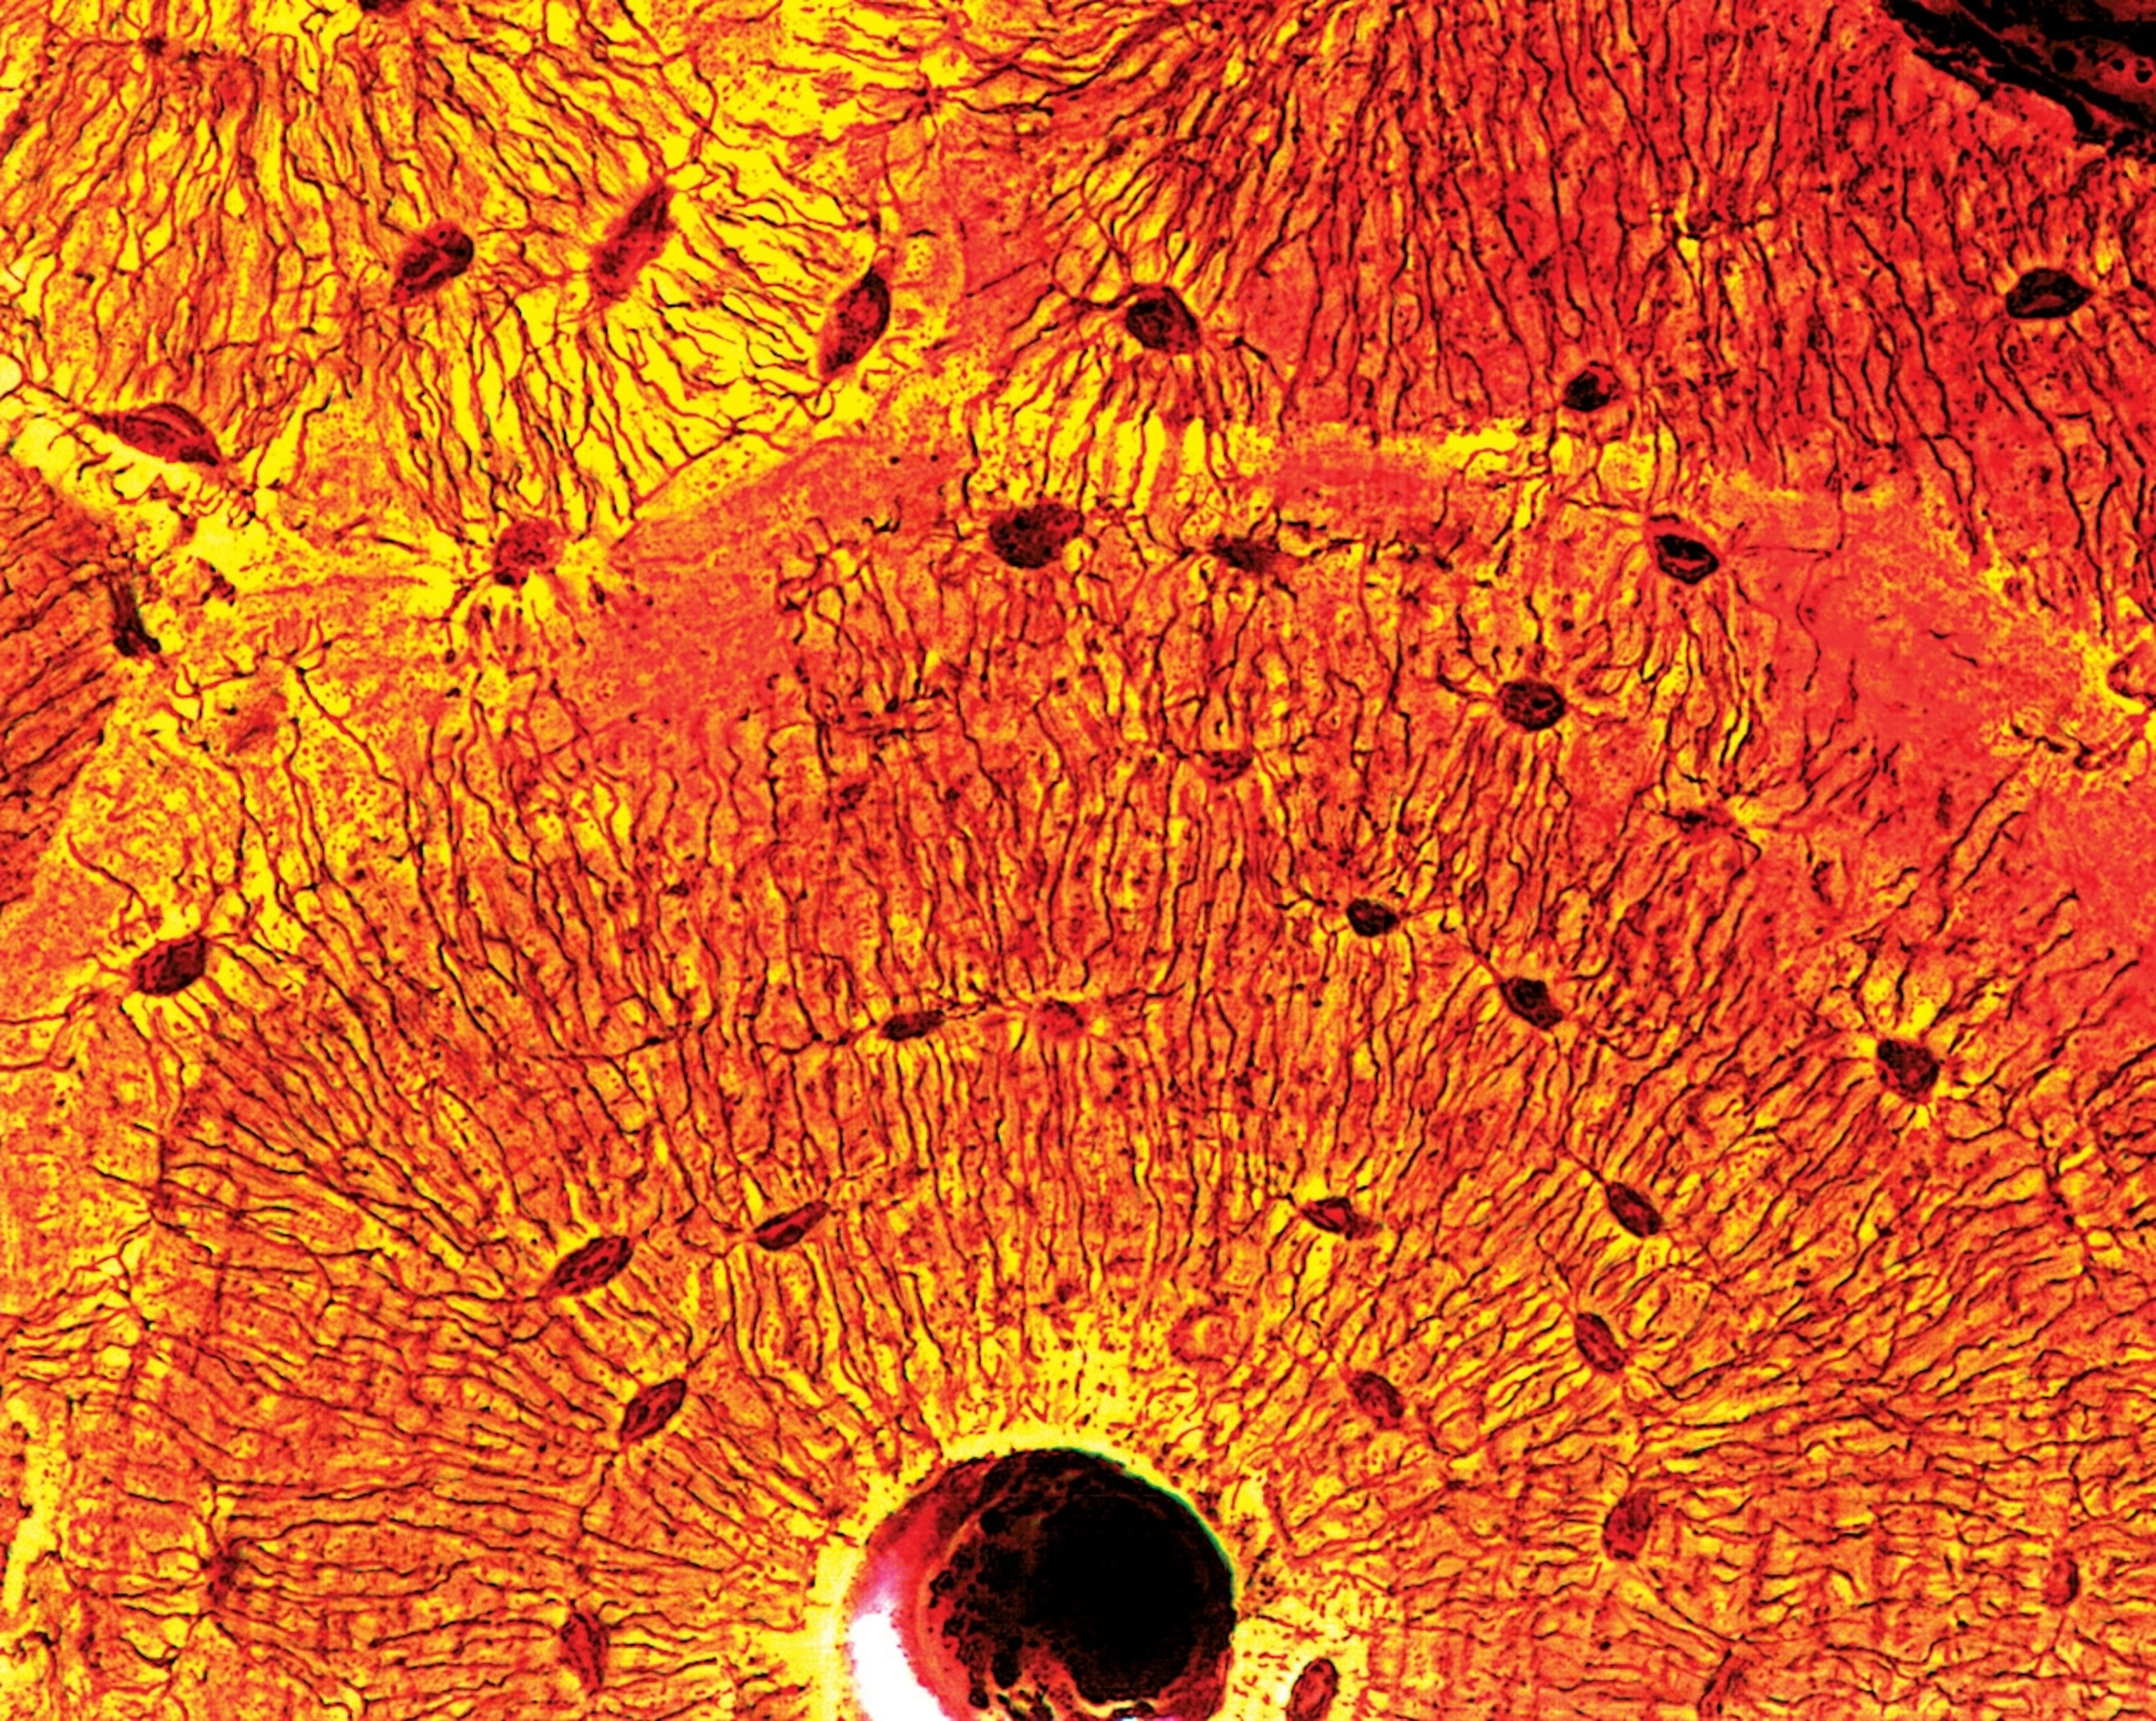

The process of aging begins in the body’s smallest units, the cells. How and why cells age is a subject of debate, though a few mechanisms are becoming clear. In the early 1960s, biologist Leonard Hayflick discovered that cultured cells would divide only an average of 50 times before they stopped—a number that has become known as the Hayflick limit. With the exceptions of stem cells and cancer cells, this limit applies to all human tissues, though cells from older people divide fewer times.

But what makes cells slow down and die? An interesting finding is the discovery of the role of telomeres. Telomeres are stretches of DNA that cap the ends of chromosomes, protecting them from damage and keeping them from fusing with other chromosomes. Researchers found that each time a cell divides, about 50 to 100 of the telomere’s nucleotides are lopped off. When the telomere reaches a minimum length, cell division stops altogether.

This finding was bolstered by the discovery of telomerase, an enzyme in immortal cells (such as stem cells) that repairs telomeres after each division. The enzyme does not affect nondividing cells, such as those in the brain and heart tissues, and in cells that do divide, telomerase may promote cancer.